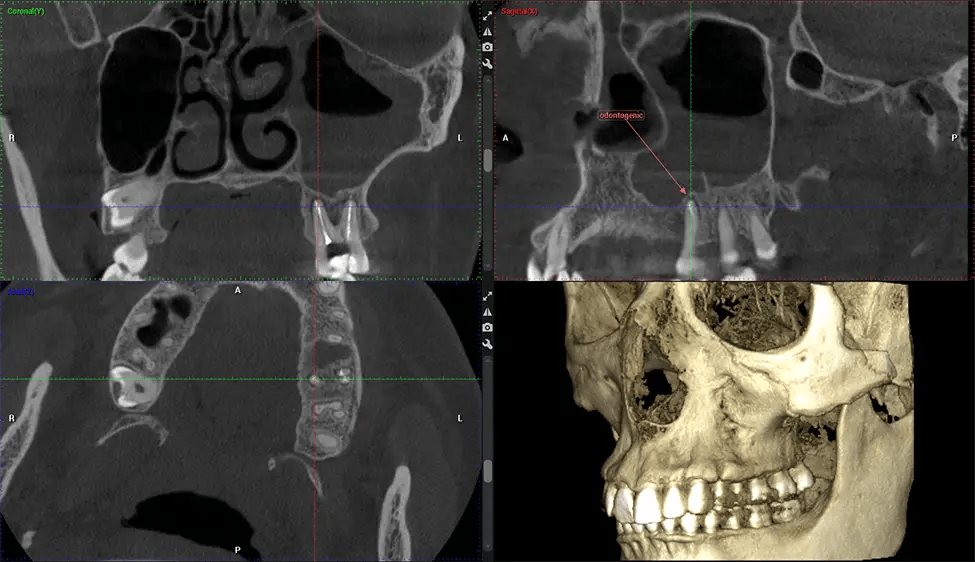

Cone Beam Computed Tomography (CBCT) is an advanced imaging technique used in dentistry and maxillofacial surgery to obtain detailed 3D images of the oral and maxillofacial structures. At Dr G Dental Studio, our CBCT scanners utilize a cone-shaped X-ray beam and a specialized detector to capture images from different angles. A computer then combines these images to create a 3D representation of the patient’s oral anatomy.

This 3D scan, called cone beam computed tomography, gives your dentist a more complete image of your oral anatomy and disease processes than a traditional X-ray. Unlike conventional X-rays, which capture a 2D image of your mouth from various angles, a 3D scan takes multiple digital X-rays for one image. It provides a complete view of your jaw, teeth, nerves, and soft tissues. This enhanced view allows dentists to detect minor issues not visible in traditional 2D scans, such as impacted wisdom teeth or bone fractures in the sinus cavity.

There are many benefits to using CBCT technology, especially compared to the traditional 2D X-ray format. One of the most significant advantages of CBCT scans is that they provide much more information than traditional X-rays. A scan lets your dentist see images from all angles of your jaw and mouth, including your sinuses, nasal cavity, cheekbones, and other surrounding areas. This added information helps your dentist craft a comprehensive treatment plan that addresses all aspects of your oral health.

After the scanning process, the captured X-ray images are processed by the CBCT software, which applies algorithms to reconstruct a detailed 3D image of the scanned area. The software compiles these individual X-ray images and creates a digital 3D representation of the patient’s anatomy. The reconstructed 3D CBCT image can be viewed and analyzed by the dentist or radiologist. This image can be manipulated, rotated, and zoomed in or out to examine specific structures and evaluate the patient’s condition.